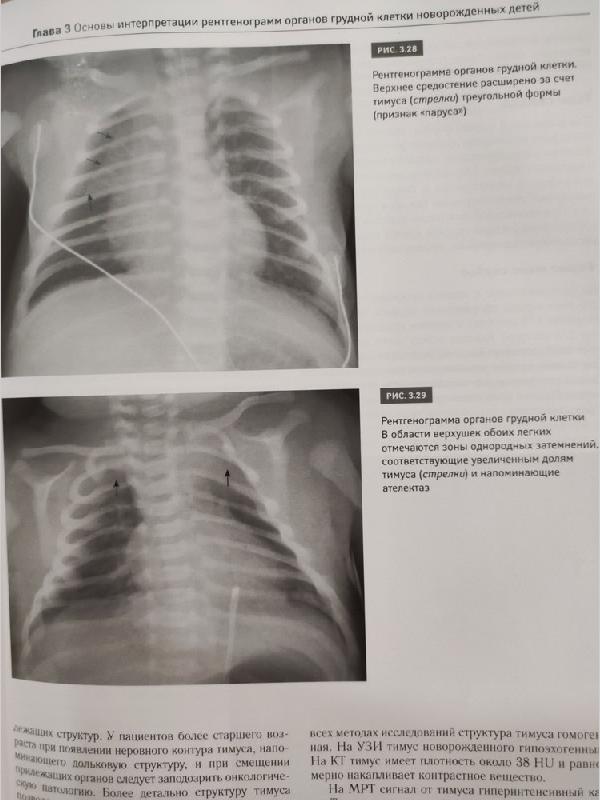

Рентгенодиагностика заболеваний легких у новорожденных детей: монография / М.В. Дегтярева, А.В. Горбунов, А.П. Мазаев, А.В. Ерохина. - М.: Логосфера, 2017. - 200 с. ISBN 978-5-98657-059-4 В монографии изложены основные подходы к рентгенодиагностике заболеваний легких у новорожденных детей, представлены развитие и нормальная анатомия легких, методика рентгенологического исследования, разобраны особенности интерпретации рентгеновских изображений грудной клетки и рентгеносемиотика заболеваний легких у самых маленьких пациентов. Книга содержит более 200 иллюстраций - рисунков и рентгенограмм органов грудной клетки и брюшной полости. Описаны сложные случаи диагностики и дифференциальной диагностики как редких пороков развития, так и часто встречающихся патологических состояний дыхательной системы новорожденных детей. Книга дополнена DVD с файлами рентгенограмм (цифровых и аналоговых), приведенных в книге. Данное издание предназначено для рентгенологов, неонатологов, педиатров, анестезиологов-реаниматологов, врачей скорой помощи, студентов медицинских вузов и других специалистов, работающих в смежных областях.